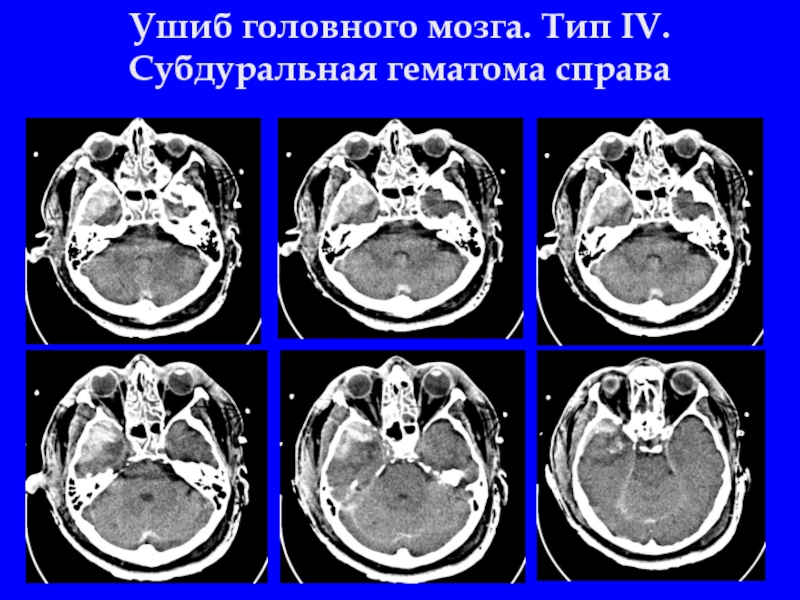

Слайд 37Ушиб головного мозга. Тип IV. Cубдуральная гематома справа